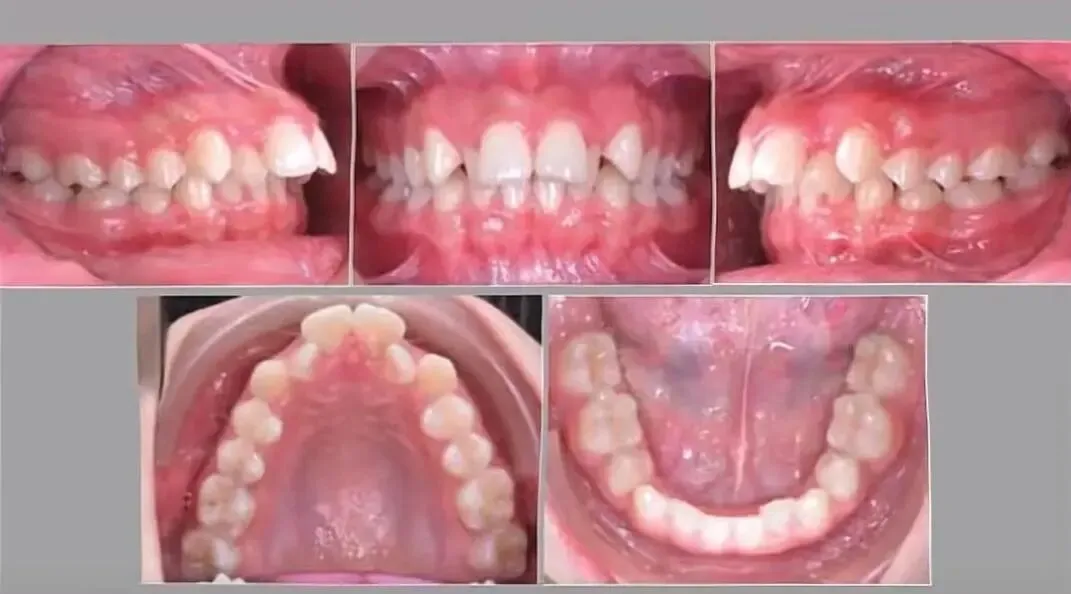

这个患者两个中切牙是舌倾的,II类2分类它会限制了下颌的前移,所以下颌处于一个后缩的状态。

这个患者他上牙弓是尖圆形,下牙弓是软圆形。上牙弓尖圆形就相当于牙弓有些狭窄,导致的下颌后缩覆盖比较大。

这个患者它两个侧前牙是偏向腭侧的,导致他下颌前伸不了处于一个后缩的状态。

这个患者两个后牙7是锁合的。两个7号牙锁合之后导致了他下颌的后缩。